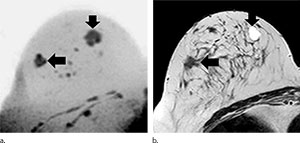

For the new study, researchers in Germany evaluated an abbreviated MR breast imaging protocol that requires no contrast agent. The protocol uses only two short sequences: the first to show the shape and appearance of the lesion and the second to display its biophysiological properties with diffusion-weighted imaging with background suppression magnetic resonance mammography (DWIBS-MRM), a technique that works by assessing the diffusion, or movement, of water molecules through tissue. Areas of restricted diffusion may indicate malignancy.

The researchers compared DWIBS-MRM to an abbreviated contrast-enhanced MRI and full diagnostic breast MR protocol in 50 women with suspicious screening mammograms and indication for biopsy.

Twenty-four of the 50 participants had a breast carcinoma. DWIBS-MRM achieved a comparable accuracy to that of the full diagnostic and the abbreviated contrast-enhanced MRI protocols. The technique yielded an excellent negative predictive value of 92 percent. Negative predictive value represents the probability that a person with a negative test does not have the disease.

DWIBS-MRM has advantages over other MR approaches, Dr. Bickelhaupt said. The MR images can be obtained in less than seven minutes, compared with more than 30 minutes for a full breast MR protocol. The mean reading time using the unenhanced DWIBS-MRM method is less than 30 seconds thanks to an innovative summation technique called maximum intensity projection, or MIP, that allows lesion assessment by reading one summation image instead of multiple single-slice images.